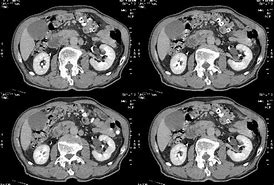

黄疸症状的发生 , 这将是胰腺癌的明显症状 。 如果你感觉不正常 , 你应该小心胰腺癌的发生 。 它是胰腺癌患者的重要症状 , 梗阻性黄疸是胰头癌最突出的表现 , 发病率超过90% 。

但在早期 , 胰体和胰尾无黄疸 。 黄疸通常是持续性和进行性的 。 当阻塞完全时 , 大便可能呈粘土色 , 皮肤可能呈棕色或青铜色并伴有瘙痒 。